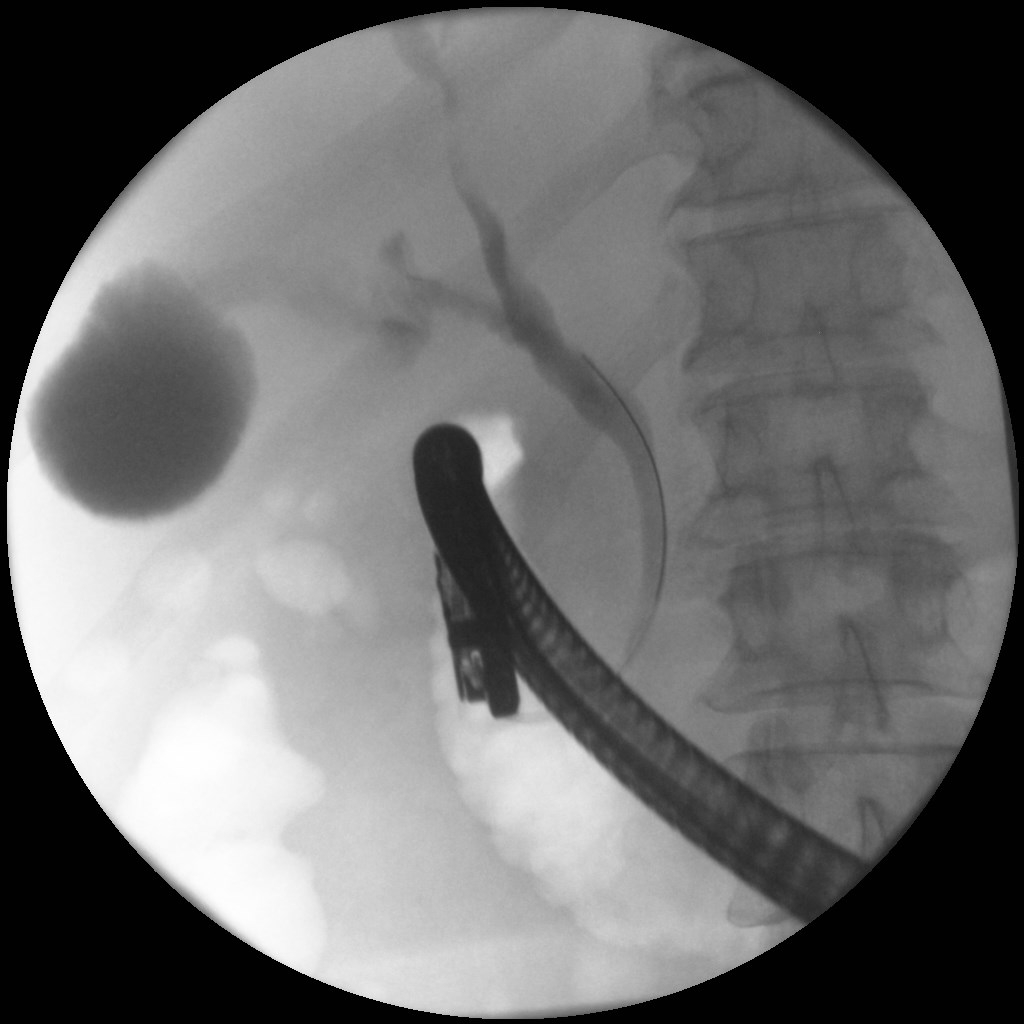

4) Χολαγγειοκαρκίνωμα πυλών ήπατος (όγκος Klatskin)

Άνδρας 61 ετών με ανώδυνο αποφρακτικό ίκτερο υποβλήθηκε σε μαγνητική τομογραφία που έδειξε διάταση ενδοηπατικών χοληφόρων με στένωση του κοινού ηπατικού πόρου και της συμβολής του δεξιού και αριστερού ηπατικού πόρου, εικόνα συμβατή με χολαγγειοκαρκίνωμα της πύλης του ήπατος (όγκος Klatskin, Bismuth IV). Επίσης συνυπήρχε θρόμβωση πυλαίας φλέβας, ασκιτικό υγρό και ευμεγέθεις λεμφαδένες πέριξ της κεφαλής του παγκρέατος και στον ηπατοδωδεκαδακτυλικό σύνδεσμο. Το νεόπλασμα κρίθηκε ανεγχείρητο μετά από συζήτηση σε συμβούλιο πολλαπλών ειδικοτήτων και ο ασθενής υποβλήθηκε σε ενδοσκοπική παλίνδρομη χολαγγειο-παγκρεατογραφία (ERCP) για αποσυμφόρηση του ικτέρου. Στην ERCP έγινε λήψη κυττάρων από την περιοχή της στένωσης με βούρτσα κυτταρολογικής, διαστολή της στένωσης με μπαλόνι και επιτυχής τοποθέτηση ακάλυπτου, μεταλλικού stent μήκους 10εκ. Μετά την ERCP, ο ασθενής βελτιώθηκε κλινικά με σημαντική υποχώρηση του ικτέρου.

ERCP

ERCP: σφιγκτηροτομή

ERCP: διαστολή στένωσης

Τοποθέτηση μεταλλικού stent